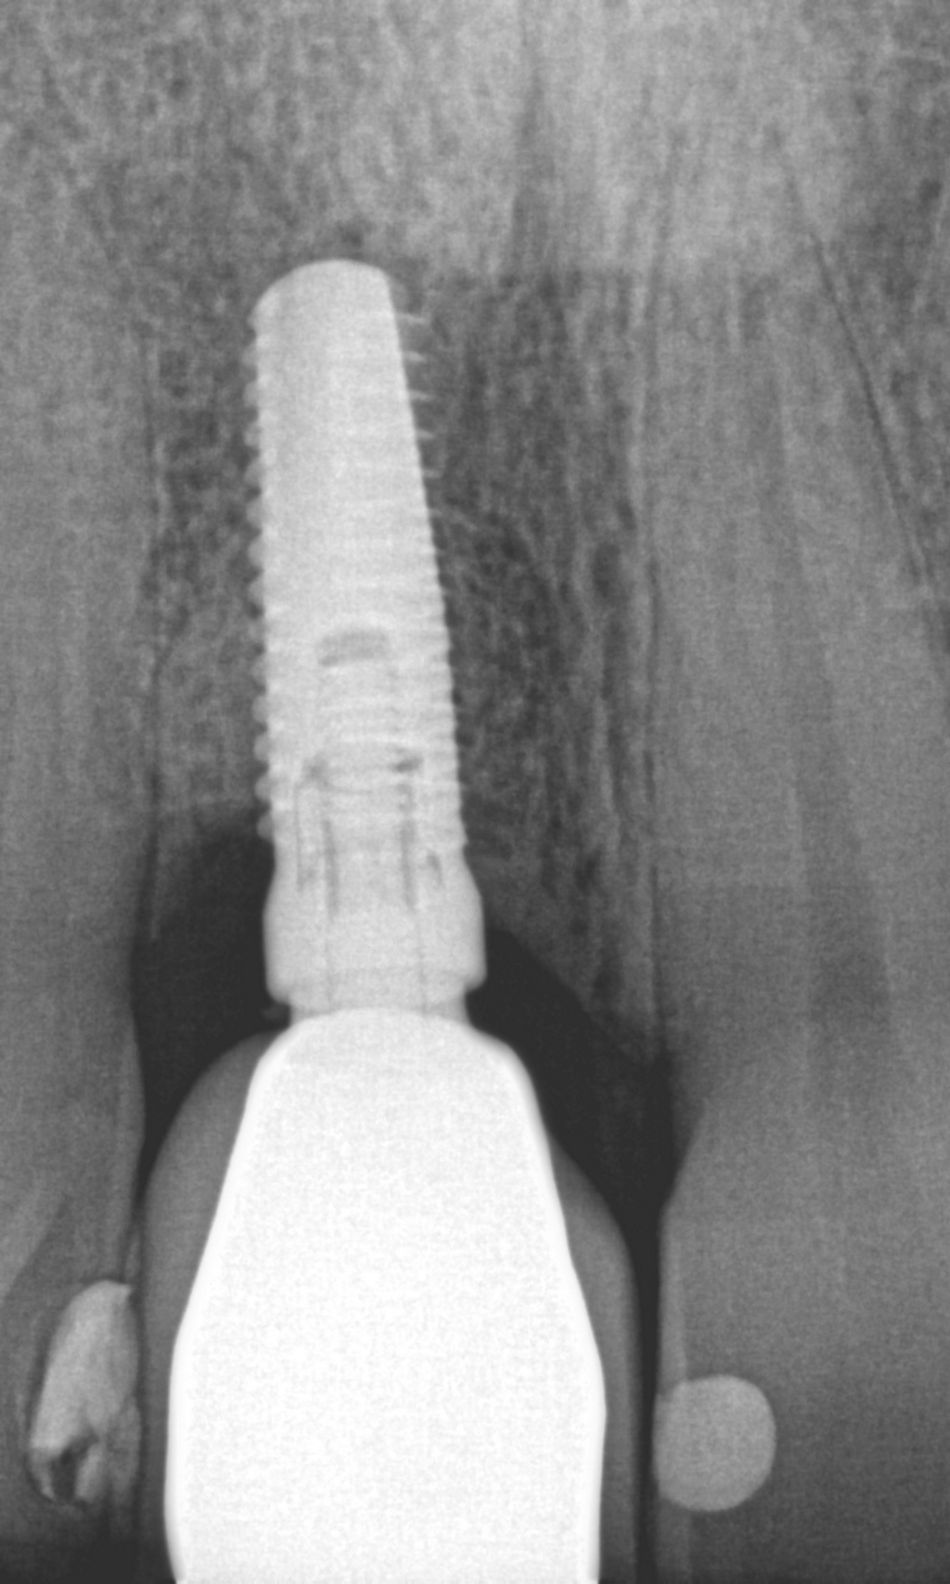

Radiographic analysis showed horizontal bone loss on neighboring teeth, particularly mesially on tooth #12, and a mixed horizontal and crater-like bone defect around the implant, which had been placed too shallowly and buccally (Fig. 2).

Fig. 2